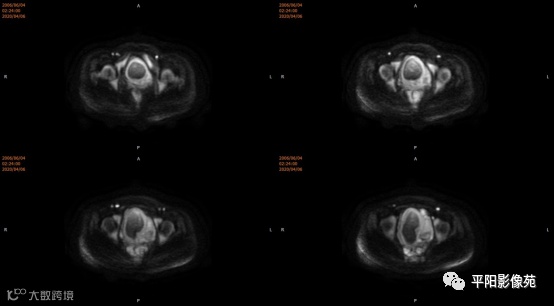

患者,女,13岁

主诉: 下腹部胀痛2+月,加重1天

现病史: 患者月经未来潮,2+月前无明显诱因感下腹部憋胀,间断胀痛,可忍耐,伴排便困难,自认为便秘引起腹胀,未在意。近1+月腹胀、胀痛次数增加,觉下腹部逐渐增大,小便正常。

子宫10cm×12cm大小,饱满,呈紫红色,子宫下段增粗膨大呈柱状,右侧卵巢可见一约18*15cm大小的肿物,表面呈紫红色,输卵管明显增粗膨大,伞端及卵巢粘连包裹于子宫后壁及侧盆壁,左侧卵巢可见一约8*7cm大小的囊肿,左侧输卵管增粗膨大伞端包裹粘连于子宫后壁及侧盆壁,直肠粘膜粘连于子宫后壁。部分大网膜粘连于子宫及卵巢表面。 注射器针头刺入子宫肌层至宫腔,抽取出大量暗红色血液,宫腔内积血,子宫缩小,子宫下段膨大,不排除生殖道畸形,双侧卵巢巧克力囊肿可能,钝性分离粘连,针头刺入右侧卵巢囊腔,吸出咖色液体约800ml,娩出右侧卵巢,切开右侧卵巢囊肿表面组织达囊壁,钝性剥离囊肿,剥离过程中可见大量黑褐色液体流出,3-0可吸收线缝合囊腔止血使卵巢成形,大小约5*6cm,同法处理左侧,使左卵巢成形,分离双侧输卵管粘连,暴露伞端,行宫腔穿刺可抽取出大量暗红色血液,考虑生殖道畸形,需改阴式手术探查,破坏处女膜,术中向患者家属交待病情,需改阴式手术破坏处女膜,患者家属表示理解,同意改阴式探查并签字。 患者取膀胱截石位,常规消毒铺巾,见外阴外观发育正常,分开小阴唇,见尿道口下方可见处女膜环,剪开处女膜环,可见阴道壁约1cm,前为盲端,分开处女膜后,于尿道下方阴道口位置,将1:10000的肾上腺素注入阴道直肠间隙,在尿道口下方阴道壁痕迹处横切约2.5cm,钝性分离,可及一囊肿,表面淡紫色,20ml注射器经此处穿刺,抽出暗褐色积血,用注射器向阴道积血方向穿刺,抽出褐色积血,探查囊腔与宫腔相通,未见明显宫颈组织,上段未见阴道粘膜,考虑宫颈缺如及生殖道畸形,清理宫腔积血,将子宫下段最低端缝合于约1cm的阴道粘膜上,形成宫颈形状,宫腔放置一根引流管,查无出血。

(左卵巢)子宫内膜异位囊肿,伴囊状滤泡形成,(右卵巢)纤维囊壁组织,未见上皮细胞被覆,符合单纯囊肿。

4.MRI检查 对软组织分辨率好,能够清晰区分子宫及阴道,对子宫内膜、结合带、肌层可清晰分辨;能明确子宫、宫颈、阴道结构异常的部位、范围、性质等。宫腔内经血潴留时,宫腔内见短T1长T2信号。